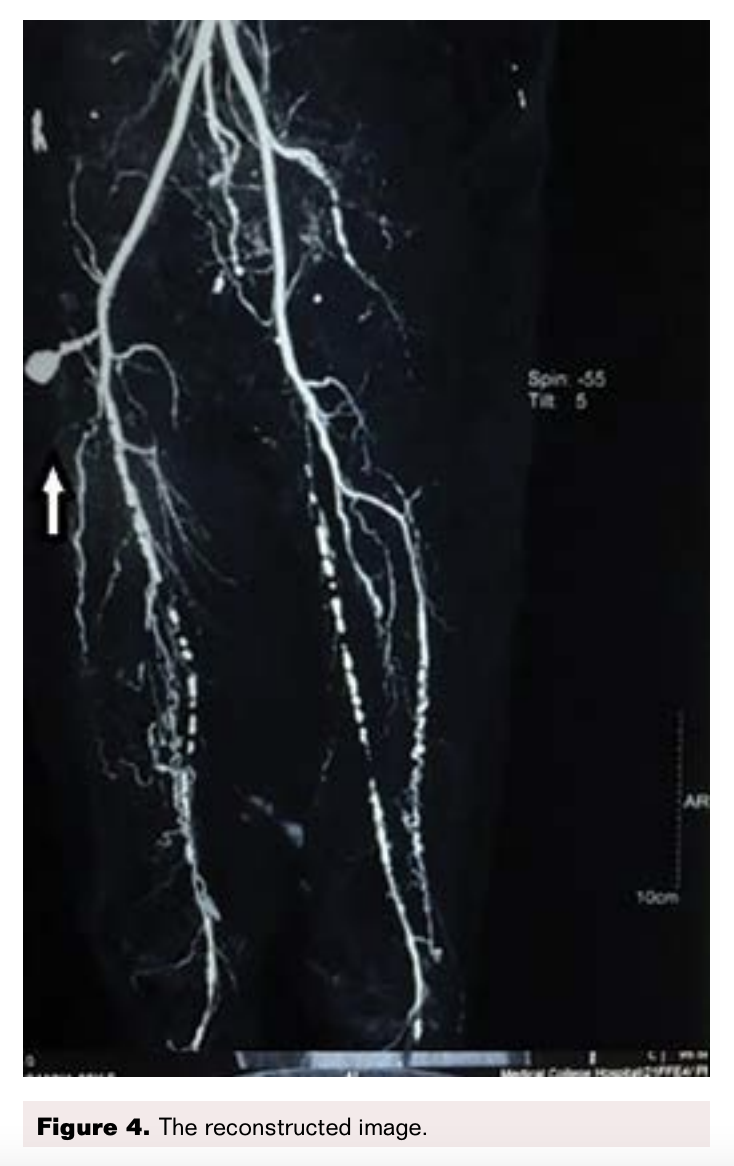

On the ultrasound arterial doppler a heterogeneously hyperechoic area was found at the upper part of the right thigh, with skin discoloration suggestive of a hematoma. This had a well-defined echogenic area with a Ying and Yang color flow, and swirling suggestive of a pseudoaneurysm. This appeared to arise from the common femoral artery (Figure 1). Since the swelling was very large, to enable further treatment decisions we sent the patient for a CT angiography of the thigh (Figures 2-5).

CT Angiogram Findings

A pseudoaneurysm arising from anterior aspect of the right common femoral artery (CFA) just above bifurcation was observed with a sac noted in the subcutaneous space that measured 1.9 x 1.4 cm. A tract from this sac had a length of 2.6 cm and arose from the CFA. A hematoma was noted in the anterior and medial aspect of the thigh in the subcutaneous space adjacent to the pseudoaneurysm (Figures 2-5).